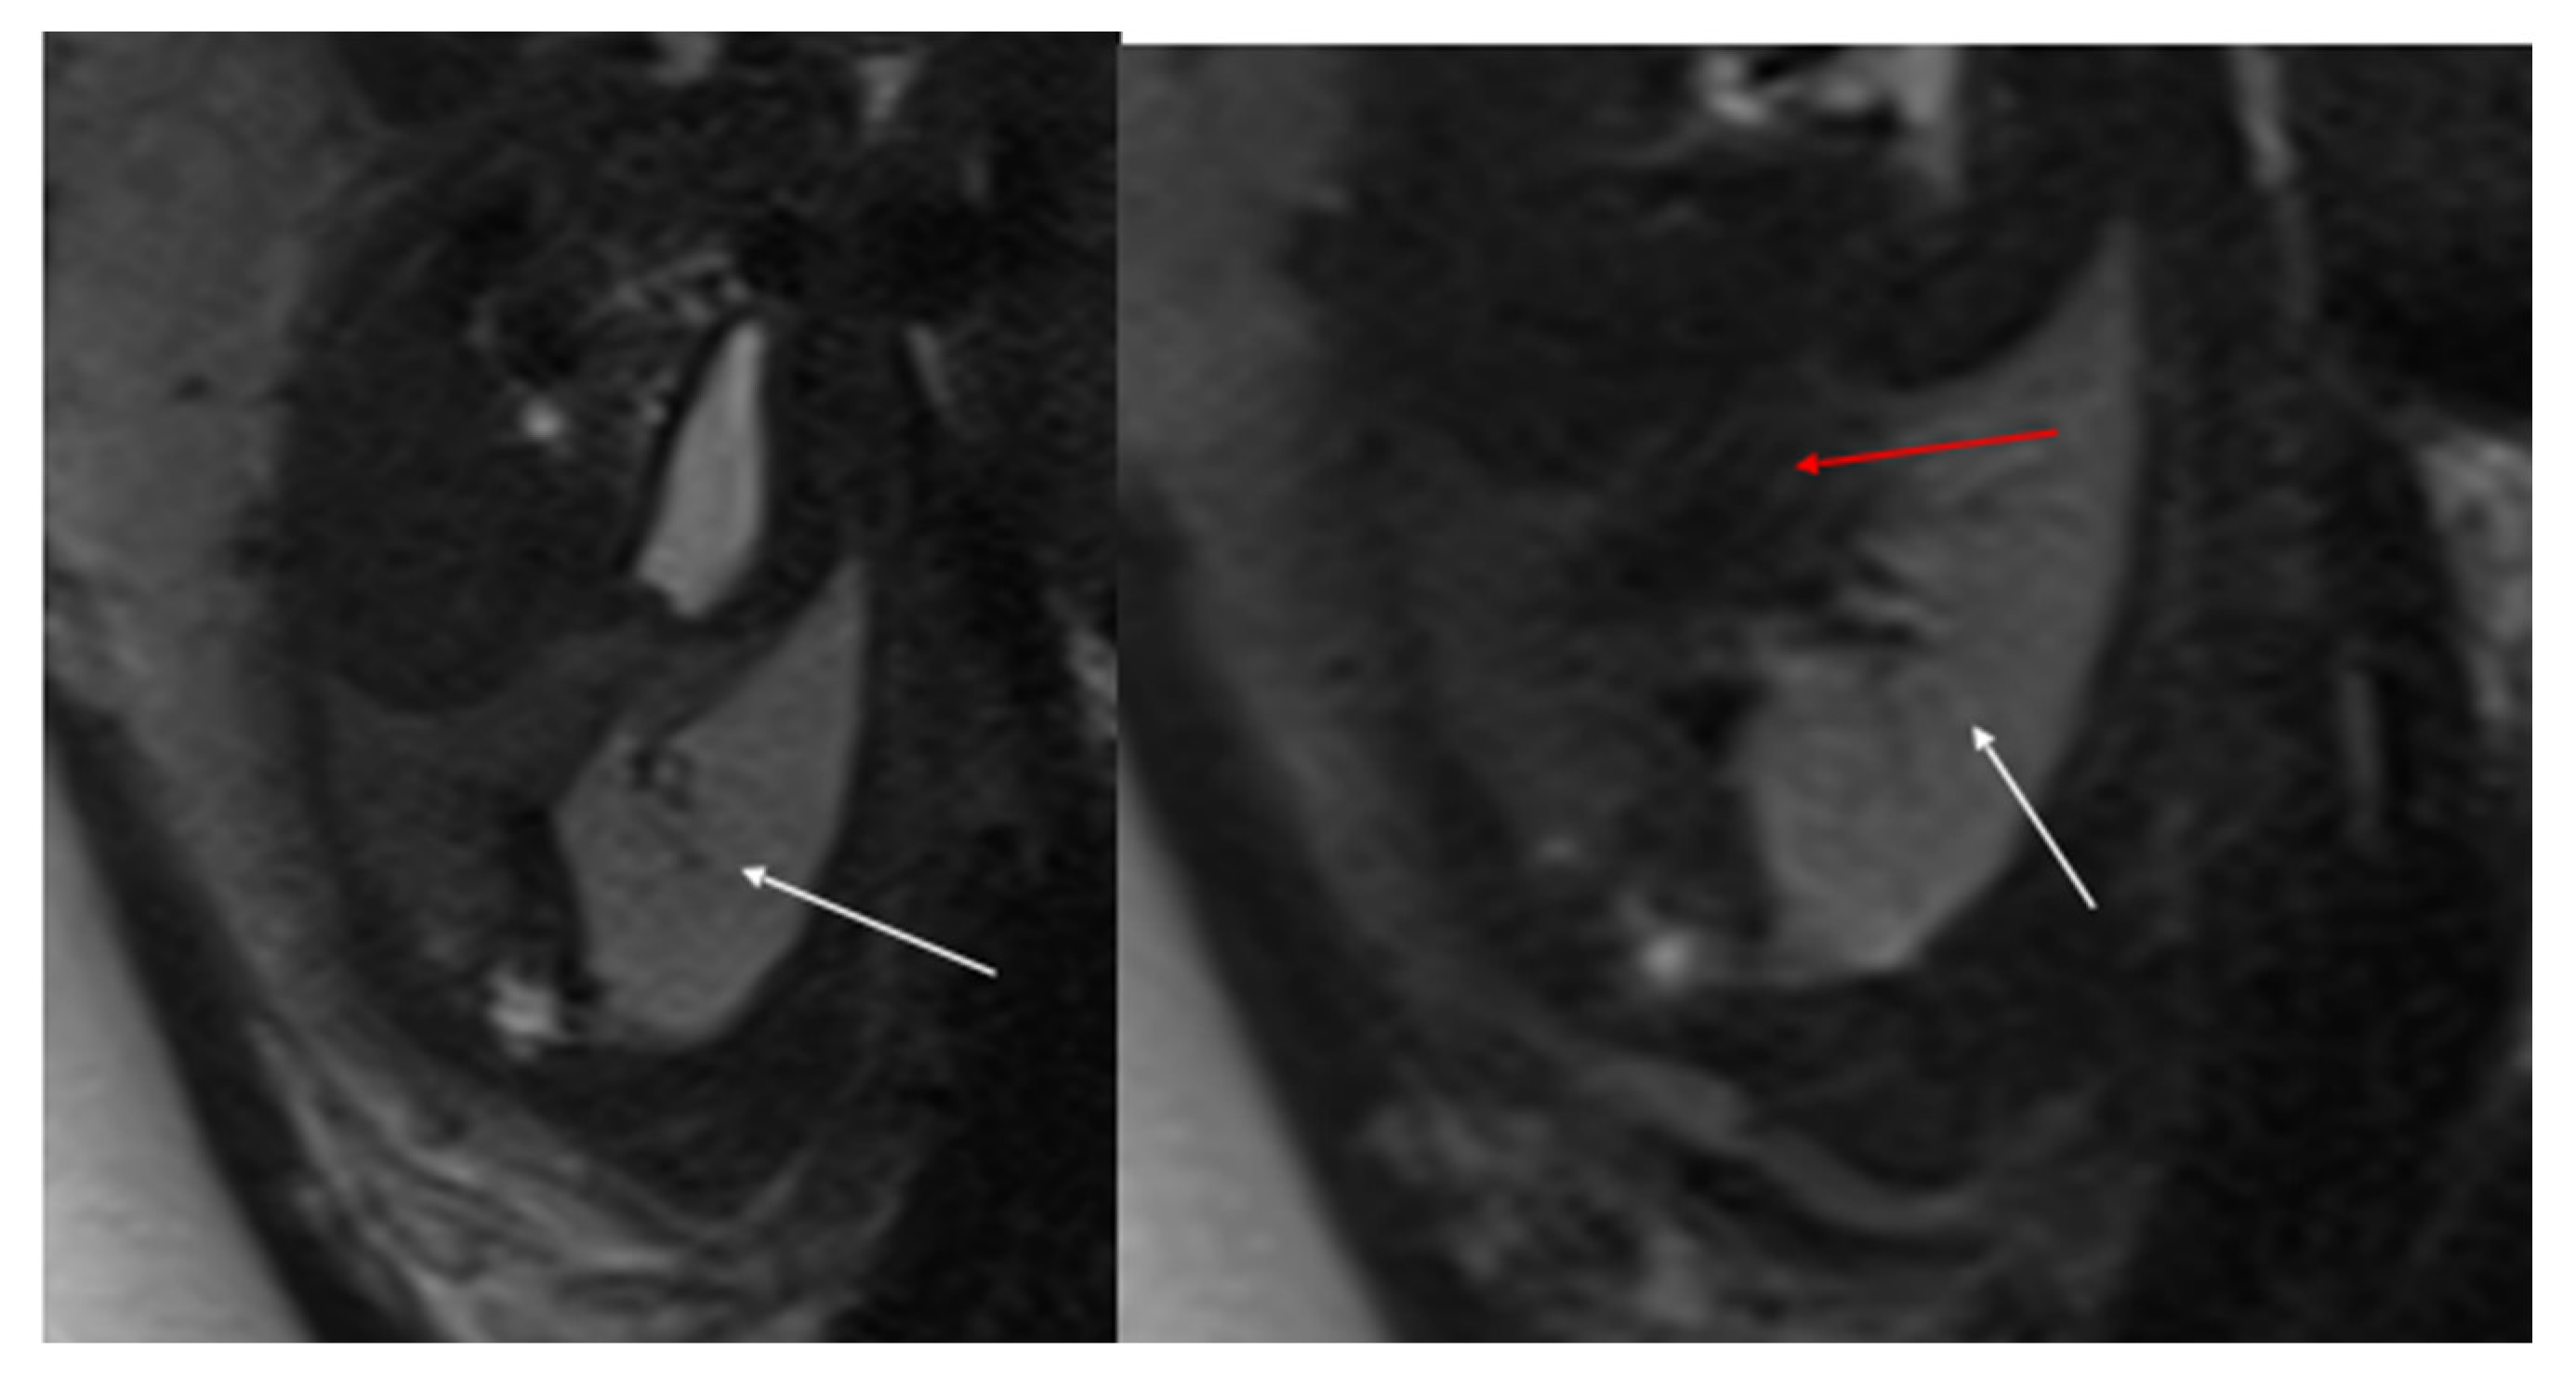

Figure 1. CPAM type I. HASTE oblique sagittal (a) and True FISP (b) MRI scans taken at 28 weeks of gestation reveal a large fluid-filled mass with bright T2 signal in the right chest (arrows). This abnormality results in a shift of the heart toward the left side of the mediastinum.